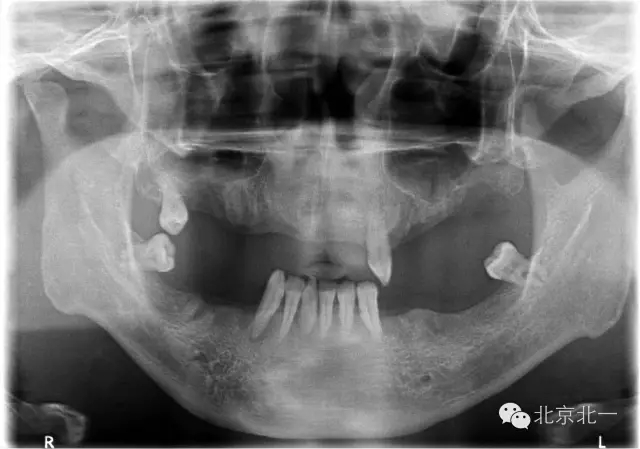

圖二:術(shù)前全景片